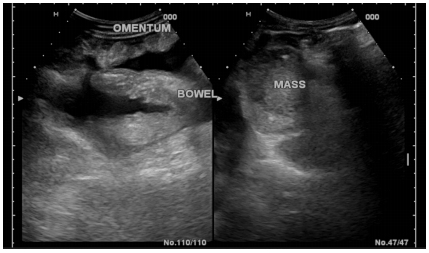

Mesothelioma (Figure 2) |

4 |

7.5 |

Figure 2 A patients with mesothelioma showing thickened omentum with heterogeneous texture and ascites.